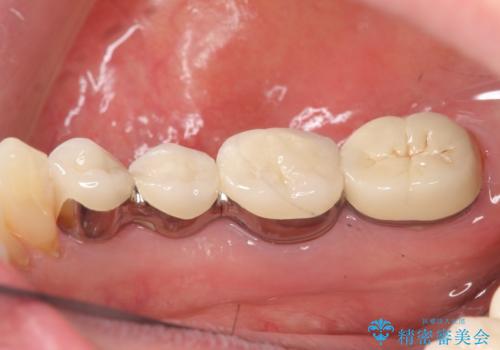

- 右下でものを咬むと痛むので診て欲しいといらっしゃった方の症例です。

右下6番目の歯を診査したところ歯根が破折していたため、保存不可能であることを説明し抜歯しました。

その後右下5、6番目にはインプラントを埋入し、右下3、4、5、6、7番の歯の補綴をオールセラミッククラウンによって行いました。

- オールセラミッククラウン…¥100,000×5、仮歯…¥10,000×5、インプラント(ストローマン)…¥200,000×2、カスタムアバット…¥100,000×2、骨増生…¥50,000費用は治療当時の料金となります

今回用いたオールセラミッククラウンはジルコニアフレームという白い素材の上にセラミックを盛っているため、審美性が非常に高いのが特徴です。

また、ジルコニアは人工ダイヤモンドの材料にも使われているほど高い強度を持っており、そのためオールセラミッククラウンは審美性だけでなく、奥歯やブリッジの補綴も可能とするクラウンです。